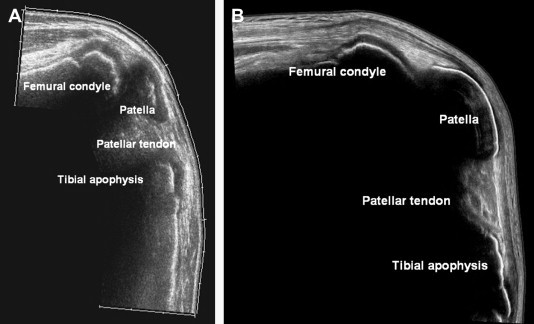

Fig. 1.

Wide sagittal US scans. (A) Normal knee of an 11-year-old boy; US allows visualization of clearly wide conjugation cartilages, hypoechoic, with femoral, tibial and patellar ossific nuclei; (B) normal knee of a 15-year-old boy; conjugation cartilages appear remarkably thinner than in the previous case and can still be seen in femoral and tibial metaphysis, while the tibial tubercle ossification center is still not fused.